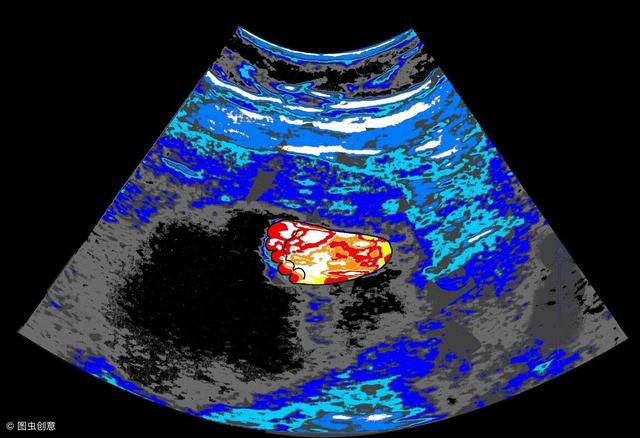

在B超的检查结果出来之后 , 医生说胎儿一切都正常 , 孕芽还有胎心都有 。 但是从验血的情况来看 , 小云的孕酮值好像是有点低 , 需要吃保胎药 。

如果说准妈妈们怀孕在四十天之内的话 , 可以验血查一下HCG值 , 超过四十天的话 , 只需要做一个B超就可以了 , 验血没有必要 。

不过 , 有种情况需要孕妈们注意:如果说在孕早期的时候 , 孕妈们出现了腹痛 , 下体有轻微的出血或者是有褐色分泌物出现 , 这时候查一下孕酮值就很有必要了 。 因为那些状况 , 都是一些先兆流产的症状 , 适当的吃一些保胎药 , 进行一些措施 , 也能起到补救的作用 。